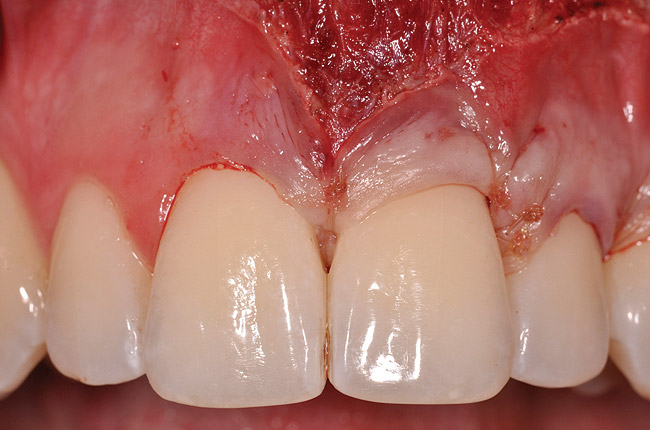

Fig 4. V-type incision to preserve the crestal portion of the papilla.

Figure 4

The flap approach follows an incision design where the crest of the papilla is preserved and a V-type incision is made in the papillary tissues (Figure 4). This allows the preexisting papillary tissues in the area just inferior to the contact point of the natural teeth affected to be used as a tissue bed to provide vascularization to the flap/dermis complex. Prior to securing the dermal matrix tissue, the papillary tissues that remain after the incision technique outlined must be de-keratinized by using a #4 round diamond bur. This allows for the introduction of initial blood flow and vascularization of the dermal matrix tissues and nourishment of the coronally repositioned flap in the critical area of the interproximal papillary tissues. After securing the dermal matrix tissue from the palatal/lingual aspect of the teeth being treated and coronally repositioning the buccal flap, closure is achieved using an interrupted sling suturing technique.